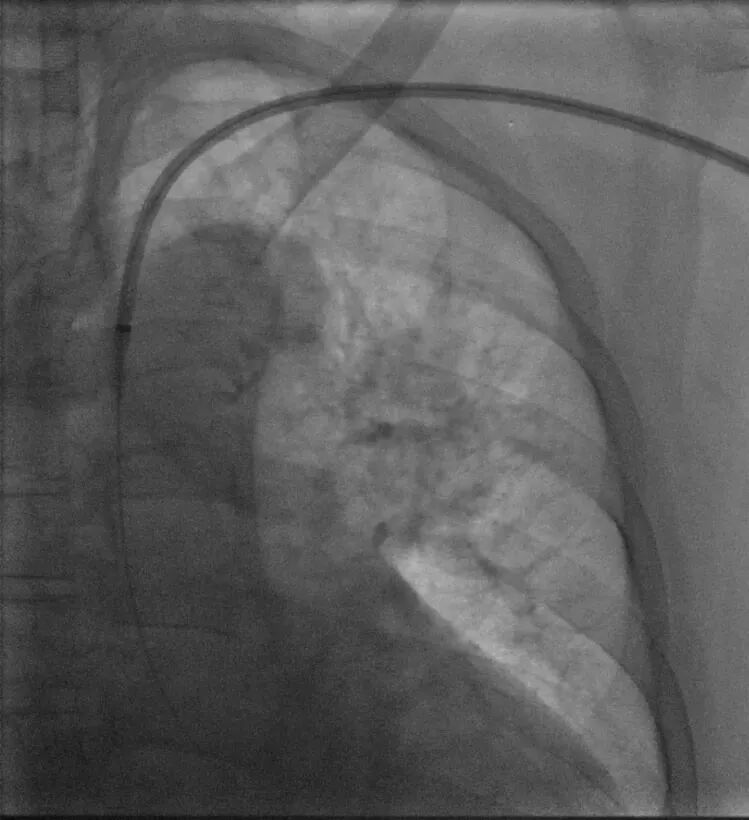

2. 术中精准测量左颈总动脉根部远端处主动脉直径,确定华脉泰科胸主动脉覆膜支架型号。右侧股动脉引入超硬导丝,退出金标猪尾导管,送入华脉胸主覆膜支架系统,精准定位于左颈总根部远端位置,释放2-3节,再次确认位置无误后,释放全部支架及后释放裸支架,再次造影示:支架位置精准、展开良好,未见成角畸形,左颈总动脉血供良好,无明显内漏。

置入华脉胸主支架

近端定位LCCA根部远端

缓慢释放2节再次确认位置

全部释放支架